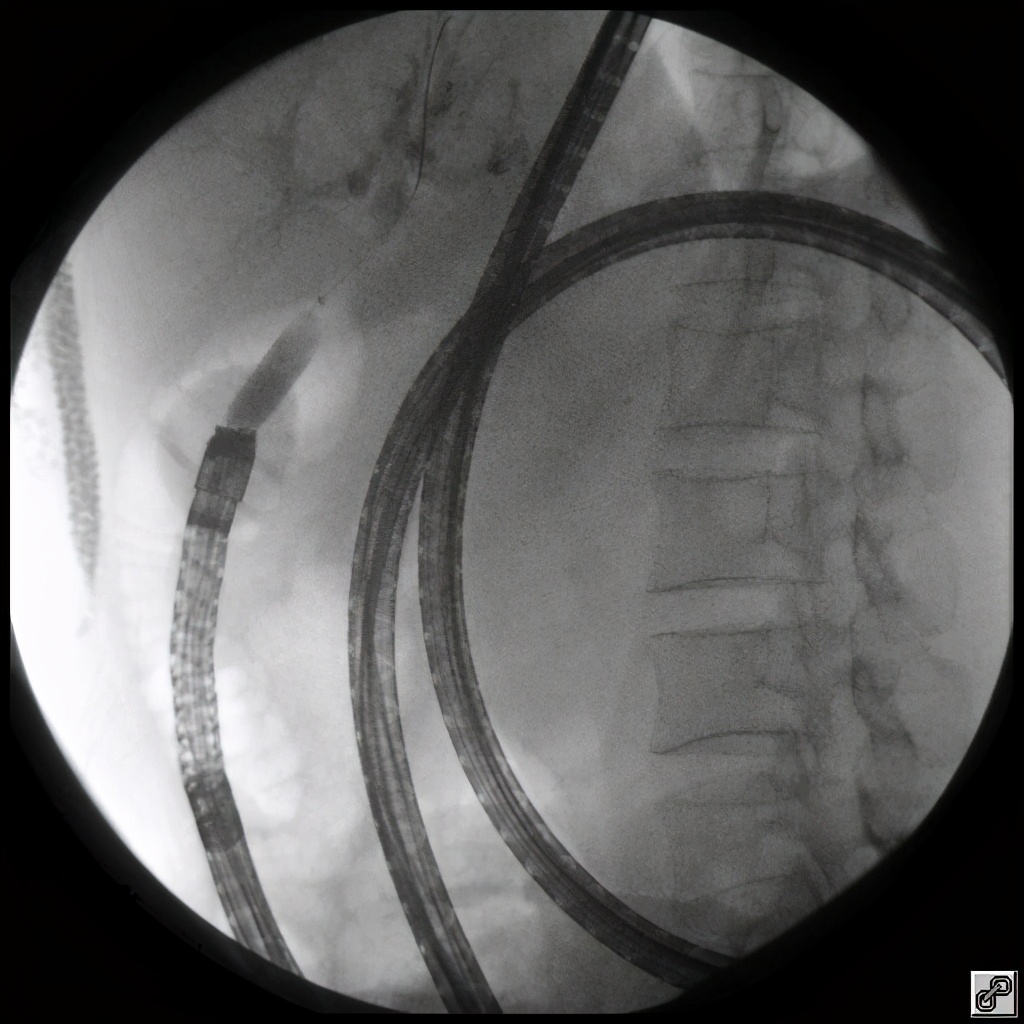

医生决定使用双气囊小肠镜辅助操作,行内镜逆行胰胆管造影术,也就是传说中的 ERCP。

但是,纵使是像张迎春医生这样的老司机,也时刻不敢掉以轻心,因为穿梭在七米长的小肠里,就好像在望不到头的隧道里找一个隐秘的出口。

我们仔细地探查了小肠的每一处,足足找了30分钟,才终于把这个针眼大小的出口找到,取出一些泥沙样的结石,然后再把出口扩大。——消化内科张迎春副主任医师

(历经30分钟,医生终于找到“胆肠吻合口”)

(对狭窄的胆肠吻合口进行扩张)